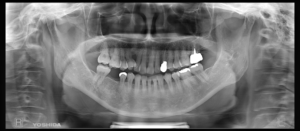

(治療前)

右下6番が欠損してることにより、噛み合わせの一部を失っていた状態です。

隣接歯があるため、ブリッジや義歯を補綴物として選択もできますが、隣接歯に負荷がかかってしまうため、予後を考えてインプラントを選択しました。

▼第一治療終了後

傷口が小さく、術後の疼痛もほとんどありませんでした。